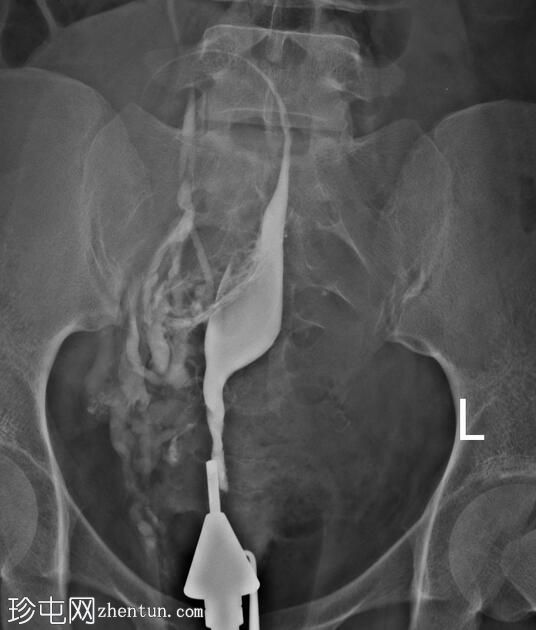

经宫颈管注入造影剂后,子宫腔被充盈。

子宫体位于盆腔中线,呈梭形。

子宫底和子宫体右侧内膜腔可见稳定的充盈缺损,经生理盐水灌注子宫声学造影(未显示)证实为子宫内膜息肉。

可见右侧输卵管走行,蠕动缓慢,未见因输卵管阻塞导致的腹膜溢出。

超声检查(图中未显示)显示,子宫右侧宫底及宫体部存在一个 8 x 9 cm 的壁内浆膜下肌瘤。该肌瘤压迫右侧输卵管的起始部及走行路径,导致其呈垂直走行。

由于输卵管阻塞,左侧输卵管从远端至峡部初级段未显影。

注射更多造影剂后,造影剂渗入子宫肌层静脉和右侧性腺静脉,随后进入肾静脉。

手术开始三分钟后,造影剂进入肾脏,充盈肾盂肾盏系统,然后流入输尿管和膀胱,形成类似于静脉肾盂造影(IVP)的影像